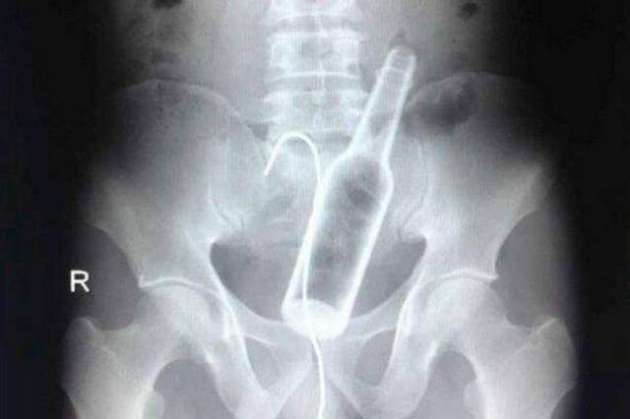

İÇİNDEKİ ŞEYE RÖNTGEN UZMANLARI ŞOK OLDU!

RÖNTGEN UZMANLARI ŞOK OLDU!

,Dünyada çekilen bu röntgenler hem röntgen uzmanlarını hemde görenleri şok ediyor...